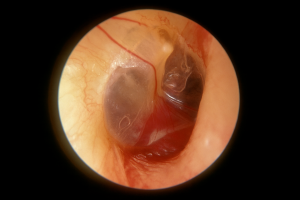

Glomus timpânico: o que é, sintomas, diagnóstico e tratamento

O glomus timpânico é um tipo raro de tumor benigno que exige um tratamento delicado de grande importância para a preservação da função auditiva.